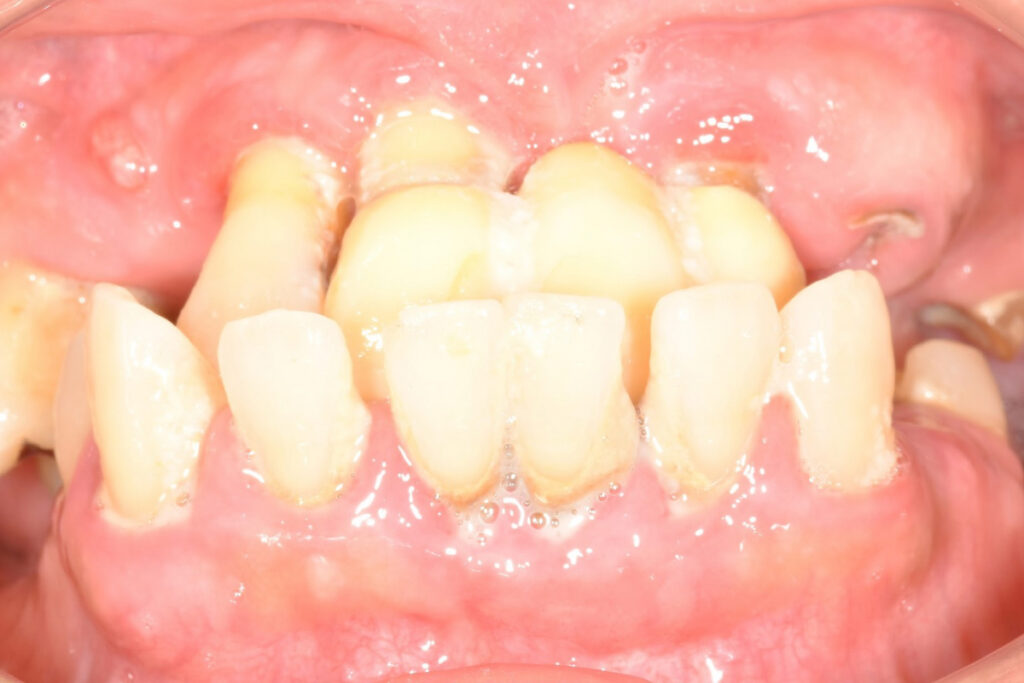

■背景

60代男性。上顎ほぼ無歯顎。食事制限が続き、外食を避ける生活になっていました。他院では、「骨が極端に薄く、通常のインプラントは不可能」と説明されました。

■問題点の整理

- 上顎骨の骨量・骨質ともに厳しい

- 通常の骨造成では長期安定が見込めない